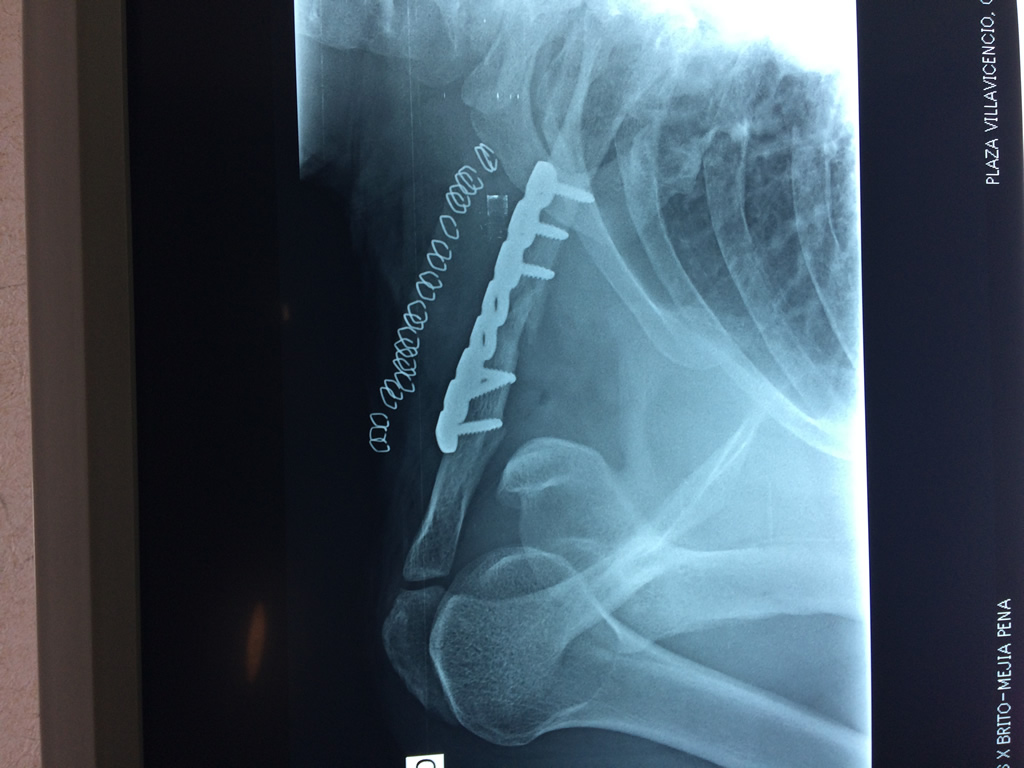

La clavícula es un hueso largo, con forma de "S" itálica, situado en la parte anterosuperior del tórax. Junto con la escápula forman la cintura escapular. Se puede palpar por toda su longitud y se extiende del esternón al acromion de la escápula, siguiendo una dirección oblicua lateral y posterior.